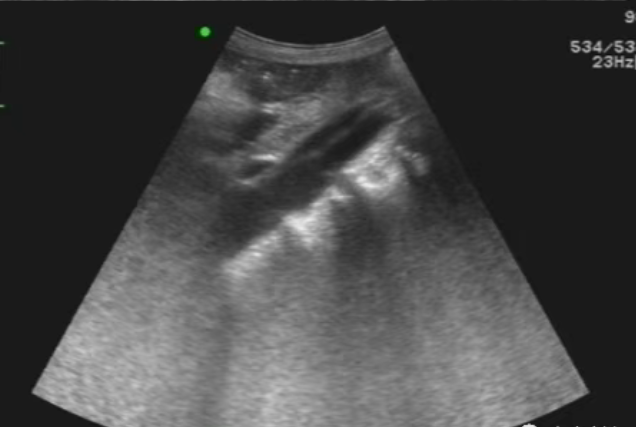

凌晨清脆的急诊电话响起,超声科的“超人”迅速将床旁超声机推至抢救室,患者烦躁不安、大汗淋漓、面色苍白,不停翻腾并指出后背像被撕开一般疼痛,初步询问患者有高血压病史,并且左下肢疼痛、冰凉,经过迅速简短查看,发现患者升主动脉及主动弓管腔内有“飘带样”回声若隐若现,并且有左室前壁室壁运动异常,左下肢动脉血栓形成并闭塞,超声医师迅速告知急诊医生,患者极大可能是主动脉夹层,急诊科迅速做出应对,最终在CT检查的共同努力下,患者确诊为主动脉夹层I型。

超声科作为急危重症影像学检查的“先遣队”,接到通知后迅速抵达急诊科,第一时间为患者开展床旁超声检查,早期识别到大动脉内“飘带样”回声,临床应高度警惕,迅速拉起急诊的“冲锋号”。超声有时也会有一些伪像,以及患者的体型、身体状况、状态,还有开展检查环境等的局限性,会导致诊断难度增加,不能完全明确诊断的情况,但是提供的特殊现象,临床及时针对这些异常进行其它影像学检查是非常必要的!三个科室形成“快速识别-紧急评估-精准确诊”的闭环,最终为患者后续的介入治疗抢出了宝贵的“黄金窗口期”。超声检查在急诊心血管疾病的早期筛查中,既是“快速侦察兵”,也是“精准导航仪”,未来科室将继续发挥技术优势,与临床科室紧密联动,为患者生命健康筑起更坚实的第一道防线。